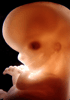

Human Embryo

Carnegie Stage 23 (56 post-ovulatory days)

Most embryos at stage 23 are approximately 56-57 postovulatory days old and measure 23-32 mm in length. Distinguishing criteria for this stage include fusion of the eyelids at the medial and lateral margins, clear distinction of the subdivisions of the upper and lower limbs, the forearms appear at or above the level of the shoulders, the superficial vascular plexus of the head is very close to the vertex, and the external genitalia are well developed but not always sufficiently to distinguish the embryo's sex.

(NOTE: These specimens are late stage 23.)

Photographs